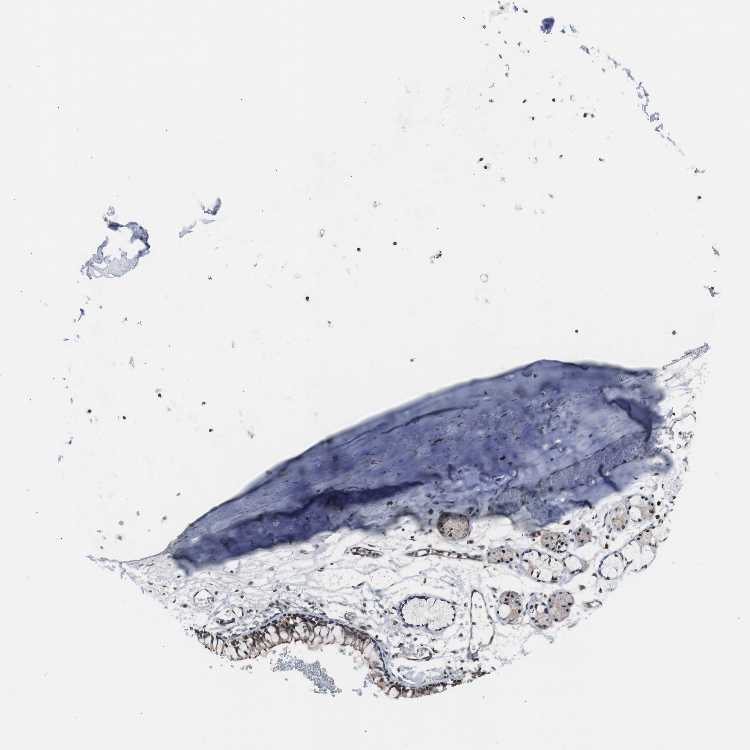

SOFT TISSUE 2 - Antibody stainingi

Antibody staining in the annotated cell types in the current human tissue is reported as not detected, low, medium, or high, based on conventional immunohistochemistry profiling in selected tissues. This score is based on the combination of the staining intensity and fraction of stained cells.

Each image is clickable and will lead to virtual microscopy that enables deeper exploration of all samples and also displays staining intensity scores, fraction scores and subcellular localization as well as patient and tissue information for each sample.

Antibody HPA006912

Fibroblasts Medium

Peripheral nerve Low